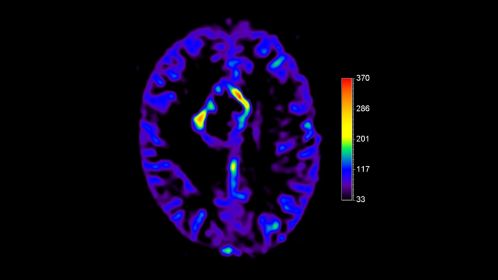

*pCASL (pseudo-Continuous Arterial Spin Labeling) ermöglicht die Darstellung der zerebralen Perfusion und funktionellen Physiologie auf kontrastfreie Weise mit geringer Verzerrung* und unter Abdeckung des gesamten Gehirns.